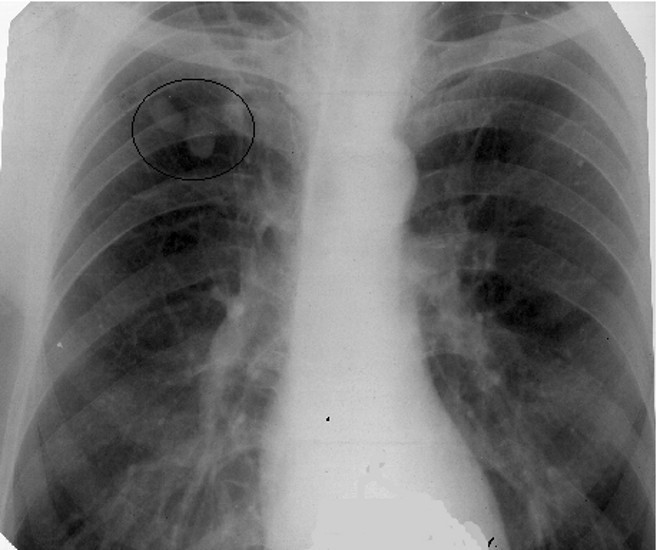

Рентгенологическая картина зависит от типа и фазы развития туберкулемы. В фазе стабилизации она выглядит в виде фокусной тени круглой или овальной формы с четкими и ровными контурами; при конгломератной туберкулеме края волнистые. В случае распада в туберкулеме чаще возникает серповидная деструкция у нижневнутреннего полюса или появляется округлая или овальная полость в центре образования.

Источником формирования туберкулем в основном служат две формы туберкулеза легких: инфильтративно-пневмоническая и очаговая. Кроме того, туберкулемы образуются из кавернозного туберкулеза посредством заполнения каверны казеозом. На рентгенограмме туберкулемы выявляются в виде тени округлой формы с четкими контурами. Туберкулёз у людей чаще всего возникает при заражении человеческим и бычьим видами возбудителя. Этот процесс называется «незавершённым фагоцитозом».